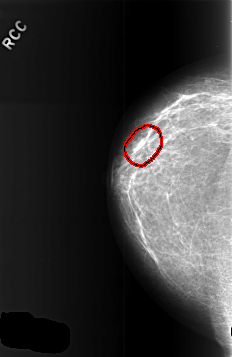

FILE: C_0369_1.RIGHT_CC.OVERLAY

TOTAL_ABNORMALITIES 1

ABNORMALITY 1

LESION_TYPE MASS SHAPE LOBULATED MARGINS CIRCUMSCRIBED

ASSESSMENT 3

SUBTLETY 5

PATHOLOGY BENIGN

TOTAL_OUTLINES 1

BOUNDARY